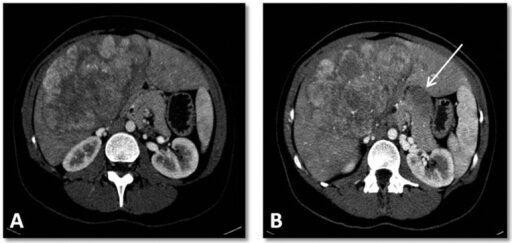

- Presença de cicatriz central em exames de imagem.